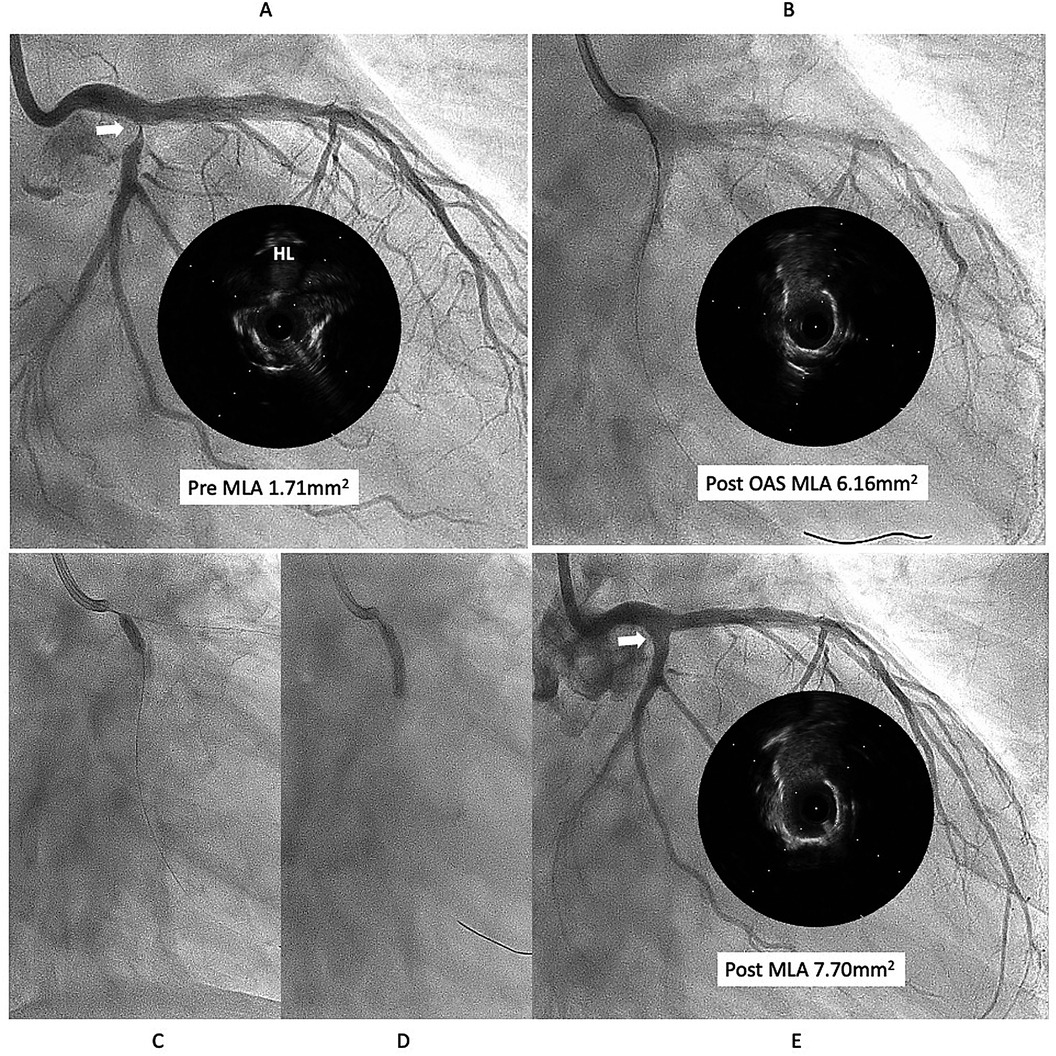

This case is a 76year-old male with chronic renal failure (CRF) on hemodialysis (HD). He admitted to our hospital due to chest pain during HD. Coronary angiography (CAG) revealed a very eccentric, calcified lesion in the ostium of the left circumflex artery (LCX) (Figure 1A), so we decided to perform PCI for this lesion. Intravascular ultrasound (IVUS) showed that the calcified plaque was protruding into the lumen, with a relatively smooth surface, indicating a non-eruptive calcified nodule (CN). The wire bias was on the plaque side, suggesting that the use of atherectomy devices would be safe and effective. Therefore, we performed debulking treatment using an orbital atherectomy system (OAS). The Diamondback 360 Micro Crown was used for the procedure at low and high rotational speed. Post-OAS IVUS demonstrated a significant cutting effect, and the lumen was enlarged (Figure 1B). The lesion was then dilated using a Wolverine cutting balloon (CB) 3.0 × 10 mm, followed by a SeQuent Please DCB 3.5 × 20 mm. The final angiogram showed no residual stenosis (Figures 1C–E).

Angiographic images labeled A to E show coronary arteries with corresponding intravascular ultrasound (IVUS) images. Image A indicates the pre-procedure minimum lumen area (MLA) of 1.71 square millimeters. Image B shows post-rotational atherectomy (OAS) with an MLA of 6.16 square millimeters. Images C and D display guidewires within the arteries. Image E depicts post-procedure with an MLA of 7.70 square millimeters. Each IVUS image corresponds to the respective angiographic findings.

Figure 1. First intervention for left circumflex (LCX) ostial lesion (white arrow). (A) The intravascular ultrasound (IVUS) showed that calcified plaque is protruding into the lumen and surface is relatively smooth, that indicates the lesion is a non-eruptive calcified nodule (CN). (B) Diamondback micro crown was used to reduce the calcified tissue, with 7 runs at low speed and 6 runs at high speed. IVUS after ablation demonstrated a significant cutting effect, and lumen was well enlarged. (C,D) lesion was dilated using Wolverine cutting balloon 3.0 × 10 mm, followed by SeQuent Please 3.5 × 20 mm. (E) Final angiogram and IVUS showed good lesion dilation (white arrow). HL indicates high-lateral branch. MLA indicates minimum lumen diameter. OAS indicates orbital atherectomy system.